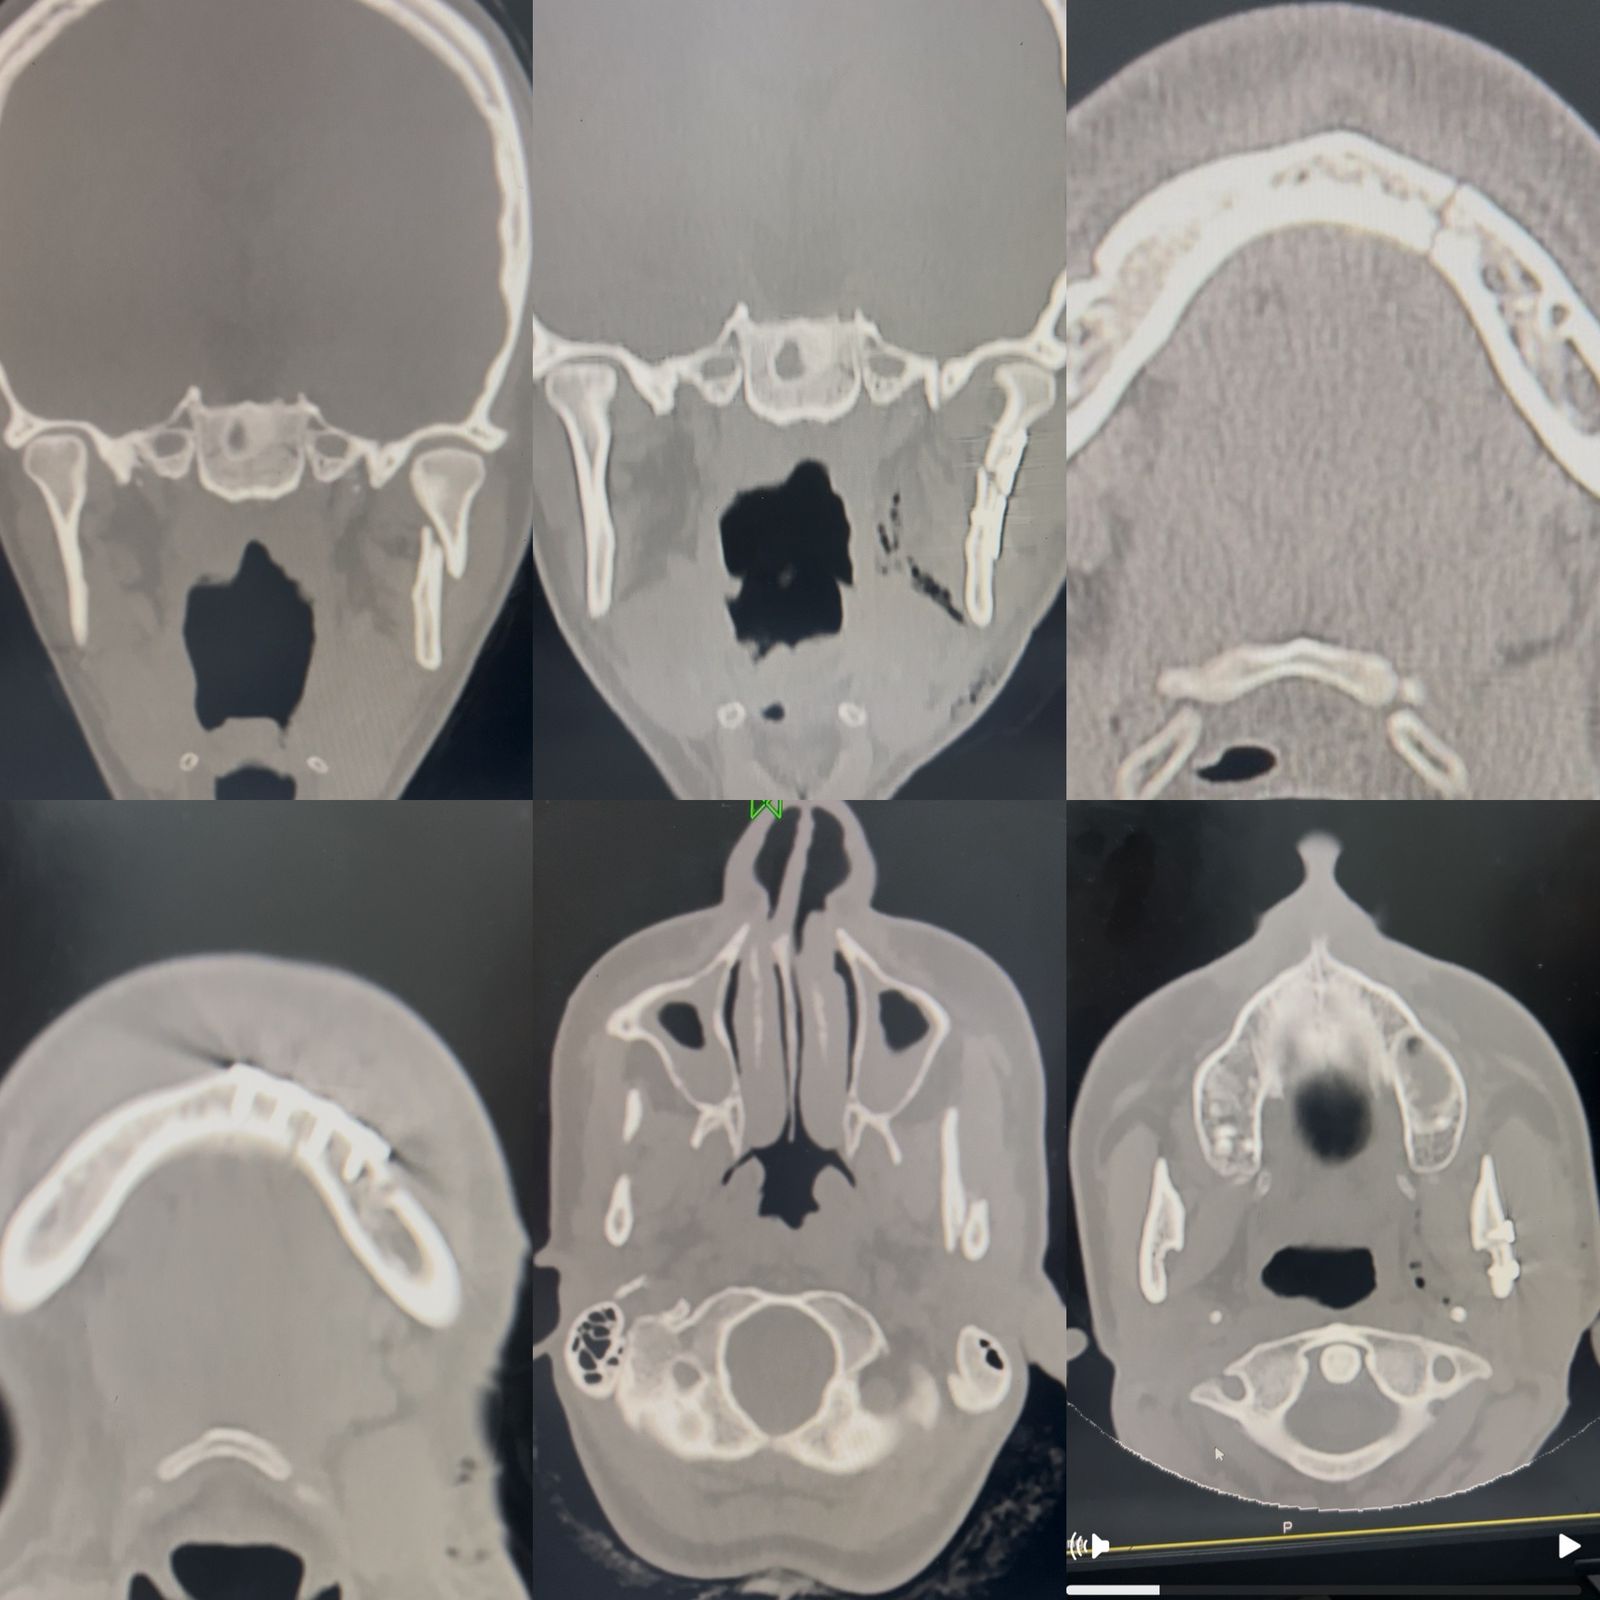

وشملت قائمة العمليات حالتين الحالة الأولى: لمريض تعرض لحادث، وكان في انتظار الجراحة بمستشفى آخر لمدة ثلاثة أسابيع، وتم بمستشفى شربين تشخيص حالته بكسر في عنق اللقمة للفك السفلي وكسر أمامي بالفك.

وأُجريت الجراحة باستخدام شق تجميلي خلف الفك للوصول إلى المفصل، وشق داخلي داخل الفم لعلاج الكسر الأمامي، مع تثبيت الكسور بشرائح ومسامير معدنية دقيقة، واستعادة الإطباق الطبيعي للفك وخرج المريض بعد استقرار حالته تمامًا.

أما الحالة الثانية فكانت: لمريض كان قد أُجري له تثبيت كسر بعظام الوجنة، وتم رفع الشريحة بعد التئام الكسر بشكل تام، في إجراء بسيط وآمن.